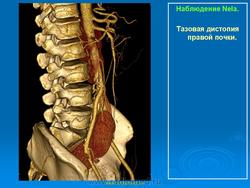

Тазовая дистопия почки

Такая аномалия встречается не часто. При этом почка находится в малом тазу. Обычно между мочевым пузырем и прямой кишкой у мужчин и маткой и прямой кишкой у женщин. При этой аномалии жалобы у пациента связаны с нарушением функции органов, соседствующих с аномально расположенной почкой. Возникают боли в прямой кишке, иногда запоры, боли во время полового акта у женщин и т.д. Иногда такую почку обнаруживают при гинекологическом исследовании, как плотное образование позади заднего свода влагалища, или при пальцевом исследовании прямой кишки.